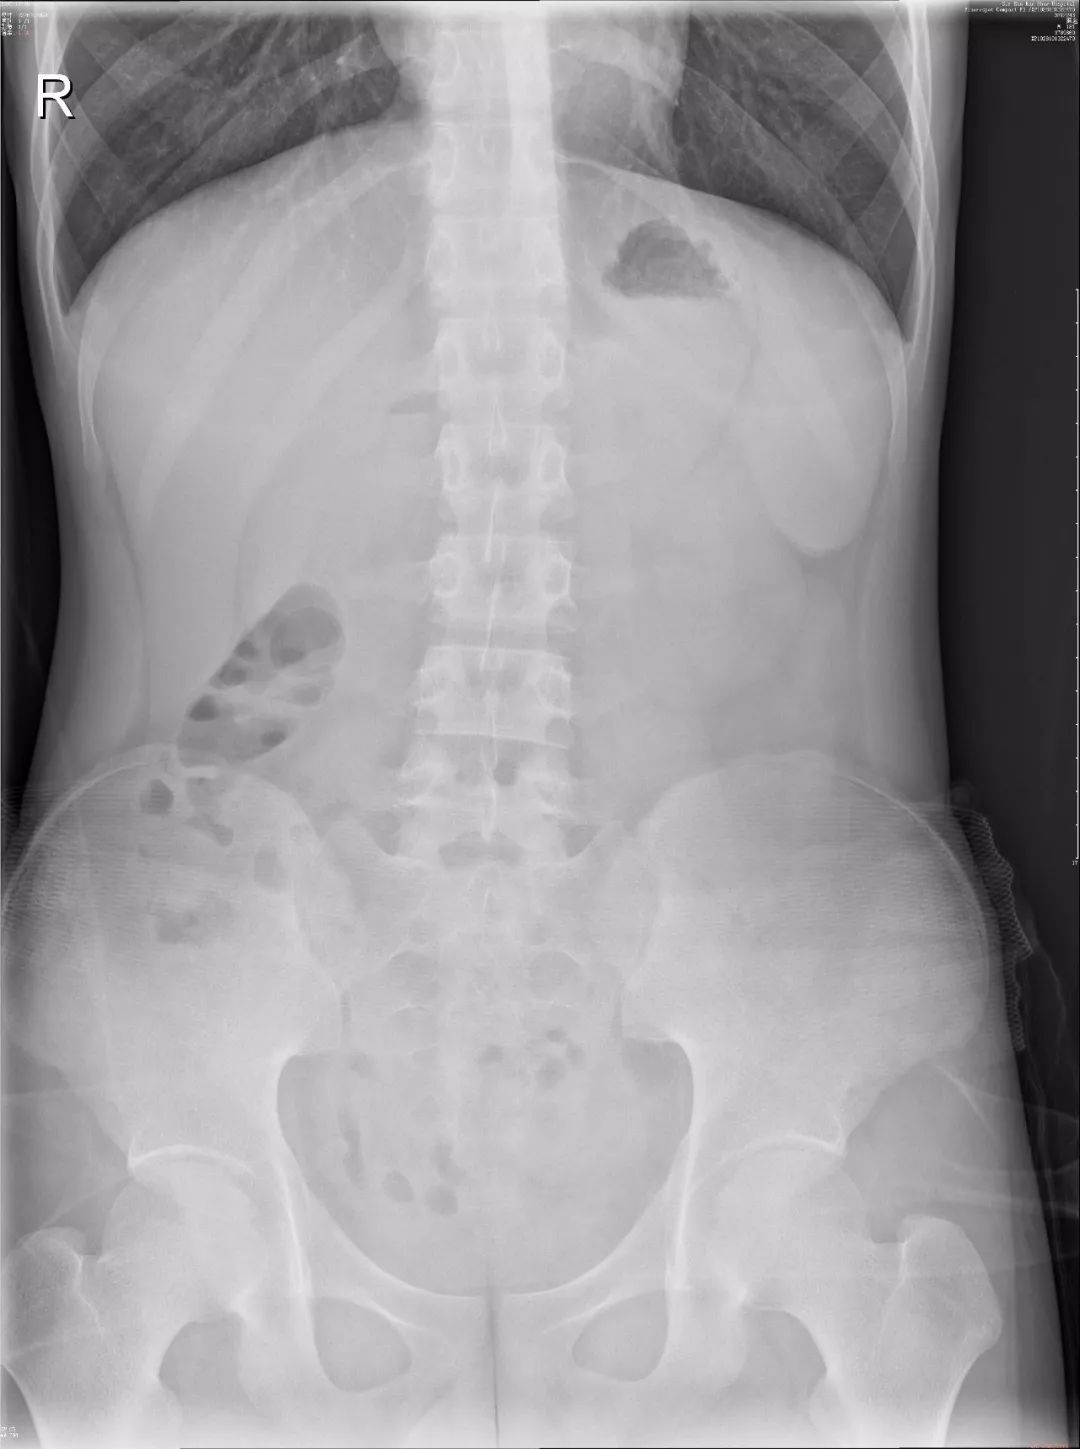

1)正常腹部立位片:两膈光整,膈下未见游离气体影。部分肠管少许积气,未见明显肠管扩张和气液平。双肾区、双侧输尿管走行区及膀胱区均未见阳性结石影。

正常腹部立位片